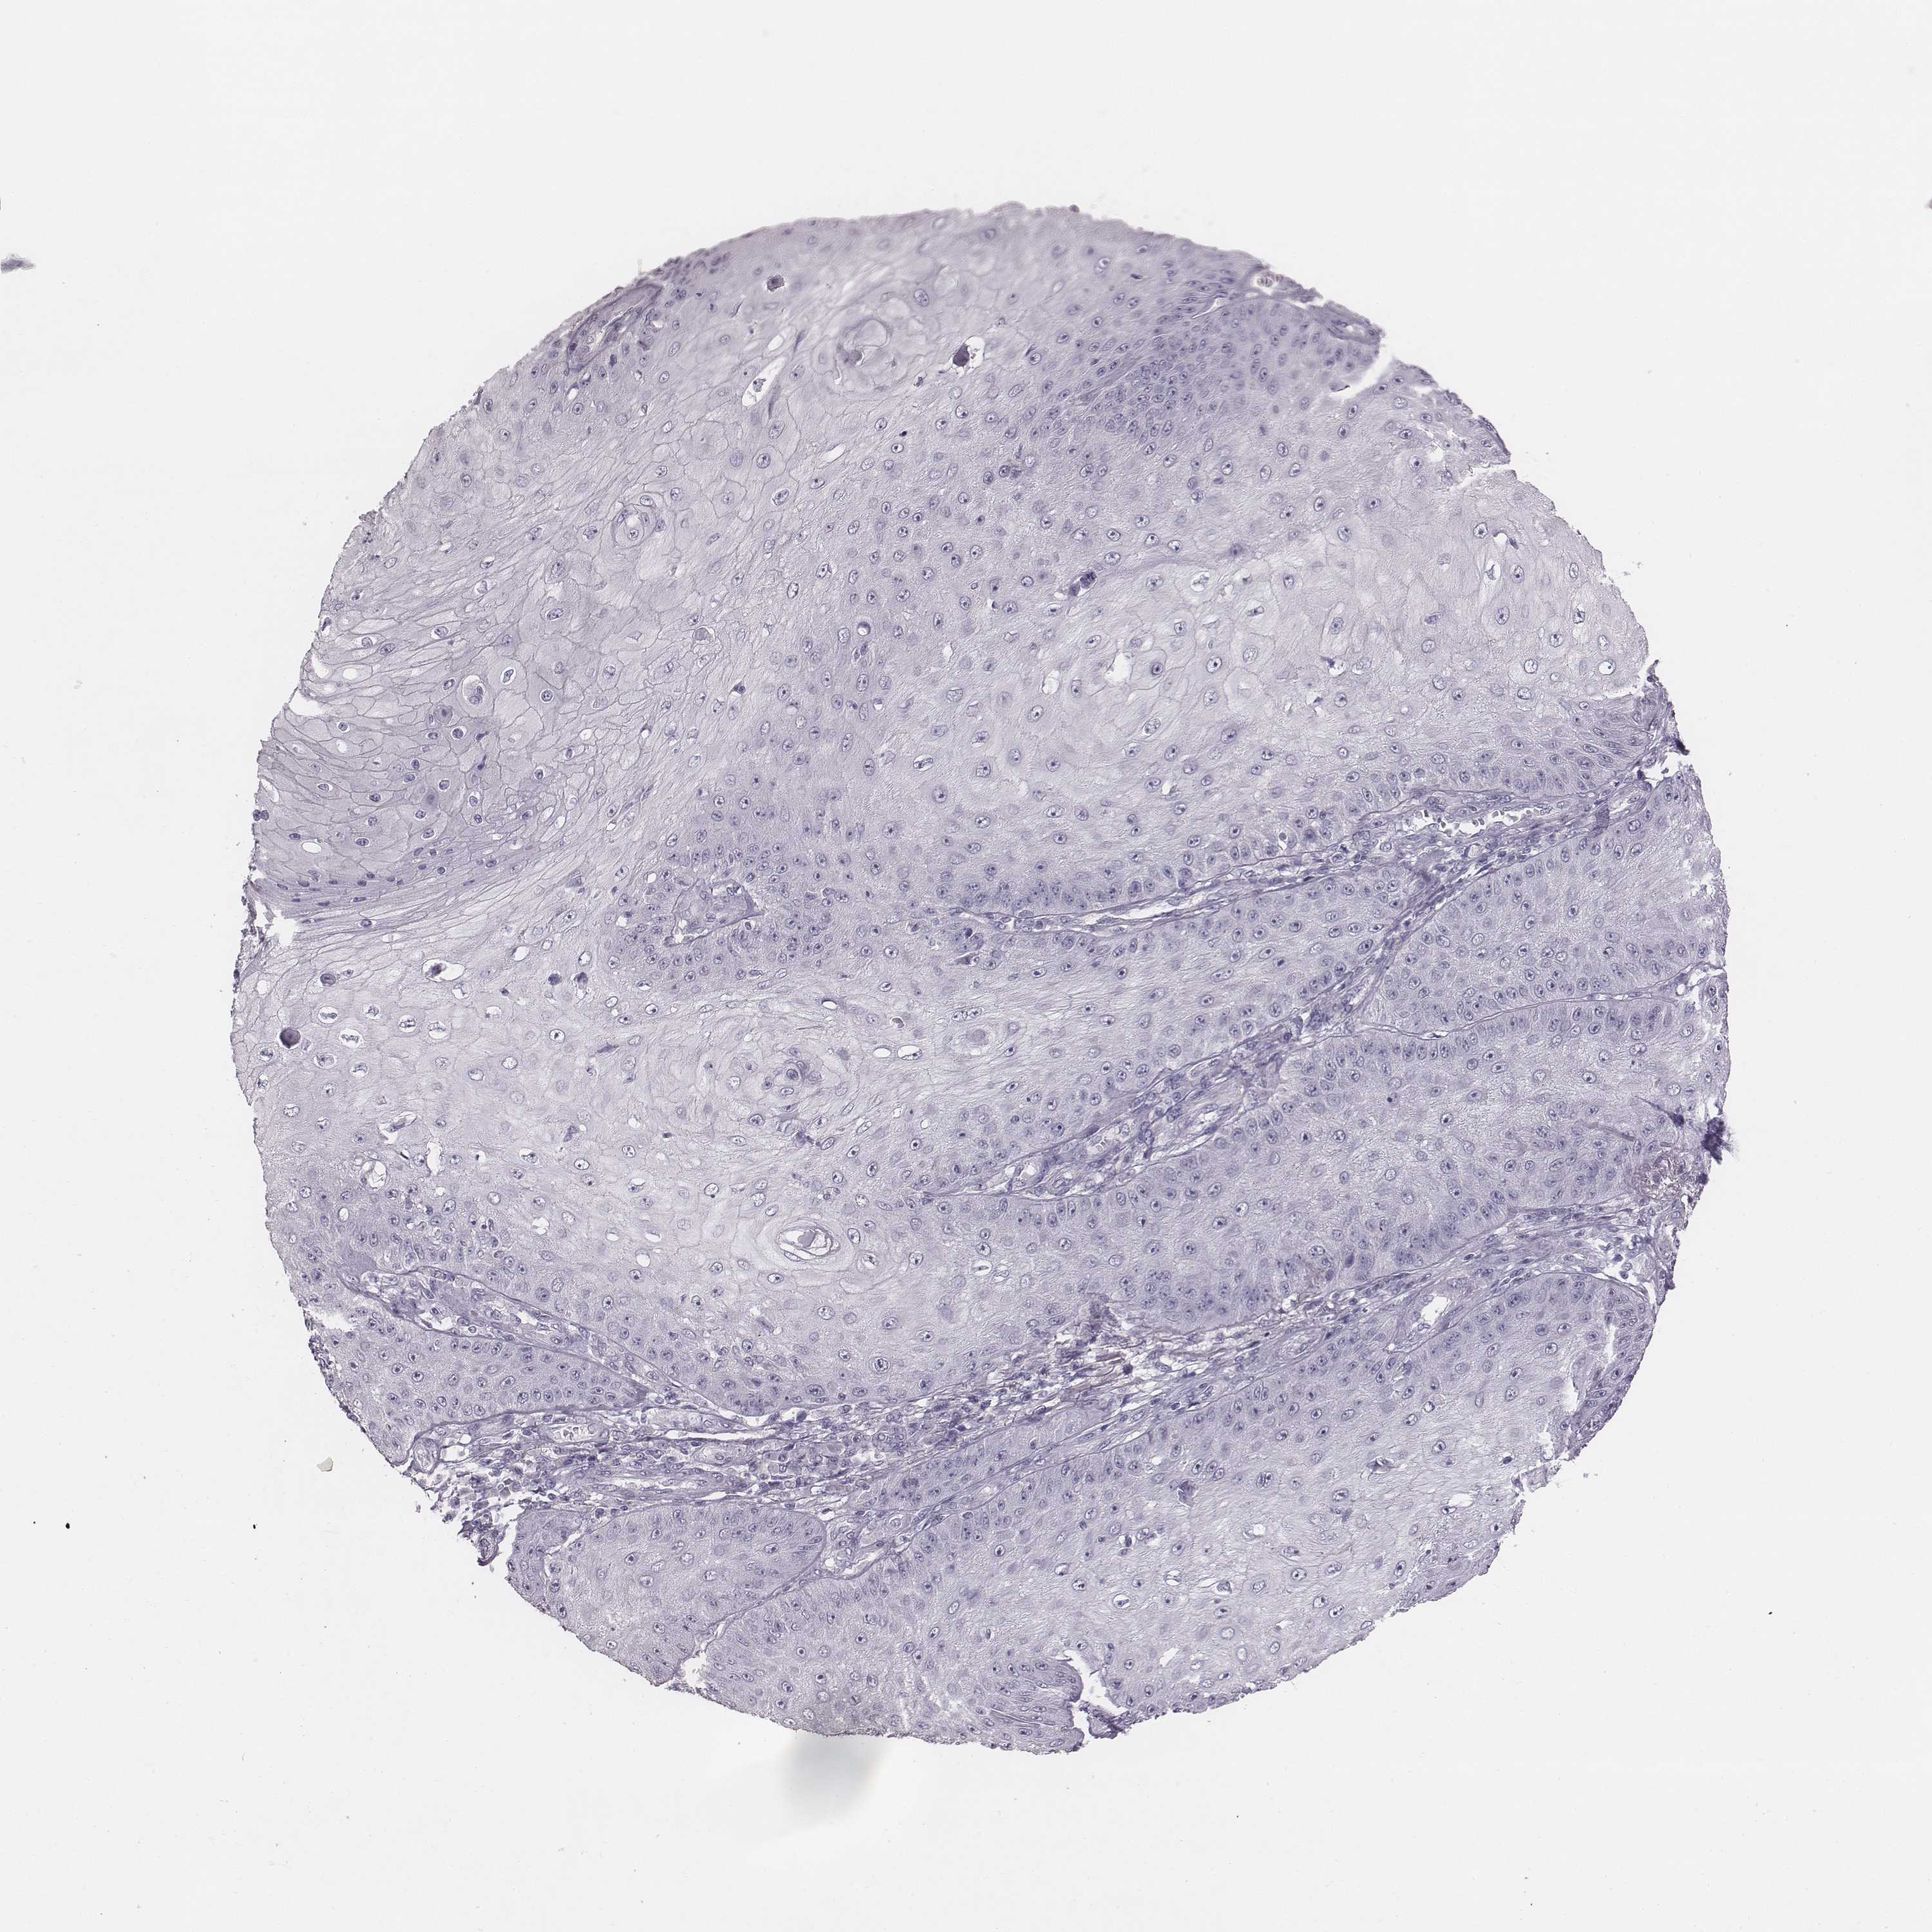

Basal cell and squamous cell cancer

SKIN CANCER - Protein expressioni

A mouse-over function shows sample information and annotation data. Click on an image to view it in a full screen mode. Samples can be filtered based on level of antibody staining by selecting one or several of the following categories: high, medium, low and not detected. The assay and annotation is described here.

Antibody stainingi

Antibody staining in the annotated cell types in the current human tissue is reported as not detected, low, medium, or high, based on conventional immunohistochemistry profiling in selected tissues. This score is based on the combination of the staining intensity and fraction of stained cells.

Each image is clickable and will lead to virtual microscopy that enables deeper exploration of all samples and also displays staining intensity scores, fraction scores and subcellular localization as well as patient and tissue information for each sample.

Antibody HPA036912

Staining

High

Strong

Quantity

Location

Squamous cell carcinoma, NOS